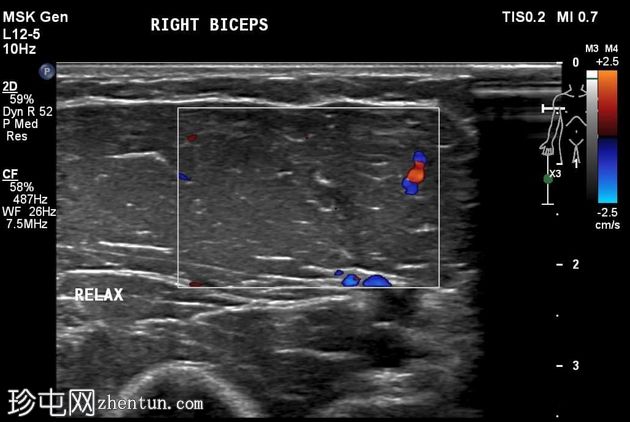

横断面

静息状态:肱二头肌短头和长头肌肉结构正常。肌腱和肌腱连接处完整,仅有轻微的断裂或积液迹象。

肘关节屈曲及肌肉收缩动态成像:肱二头肌短头和长头肌纤维之间出现充满液体的裂隙,提示局部肌筋膜分离/拉伤。未见肌纤维全层撕裂。肱二头肌远端止点正常。

诊断:肱二头肌短头和长头之间的动态肌筋膜损伤,收缩时裂隙内积液。

静息状态下的图像可能显示正常,这凸显了对有症状患​​者进行动态检查的重要性。